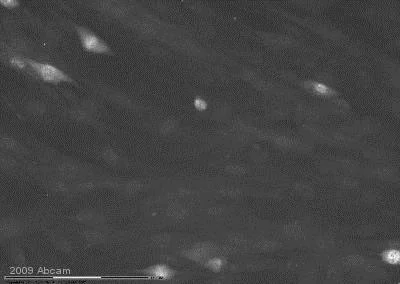

ab4821 staining JNK1+JNK2 (phospho T183 + Y185) in human foreskin fibroblasts by ICC/IF. The cells were fixed in cytoskeletal fixative, permeabilized in 0.5% Triton X-100 and blocked in 2% dillution buffer (2%BSA + 0.1% Triton X-100) for 1 hour at 25°C. The primary antibody was diluted, 1/100 and incubated with sample for 12 hours. An Alexa Fluor® 594 conjugated goat polyclonal to rabbit IgG, diluted 1/250 was used as secondary.

This image is courtesy of an Abreview submitted by Mr George Chennell